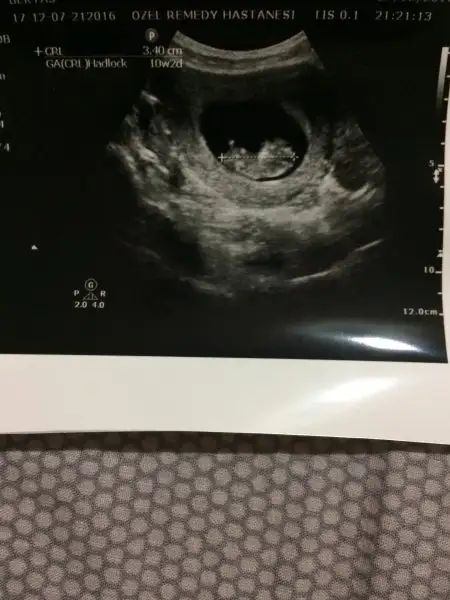

Canım benim tüp bebekle oldu başından beri nurettin bey takip ediyor sevgide , ona gitmeseydim de alattin bey e giderdim , en iyi cihazlar bu doktorlarda tavsiye ederim ..